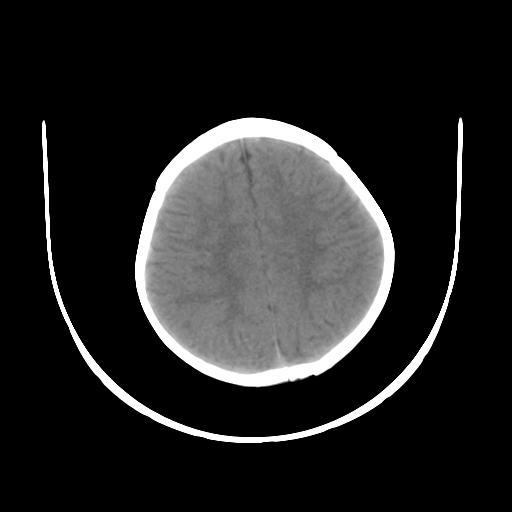

女,10个月,头外伤三天,伤后爱哭闹,吃奶少,睡觉不踏实。

左侧颞极蛛网膜囊肿

1)左侧颞极蛛网膜囊肿。2)第四脑室出血?

1、左侧颞极蛛网膜囊肿;2、第四脑室出血?3、右侧顶叶脑裂畸形伴灰质异位?